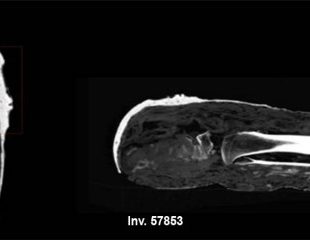

El Jueves de los Museos del 22 de enero nace del gran interés que ha suscitado la restauración de una pequeña momia perteneciente a la colección egipcia de los Museos Vaticanos: un caso de "momia-manía", un enigma resuelto gracias a investigaciones científicas exhaustivas.